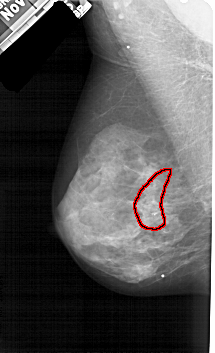

A_1605_1.RIGHT_CC

RIGHT_CC LINES 5401 PIXELS_PER_LINE 2971 BITS_PER_PIXEL 12 RESOLUTION 43.5 OVERLAY

FILE: A_1605_1.RIGHT_CC.OVERLAY

TOTAL_ABNORMALITIES 1

ABNORMALITY 1

LESION_TYPE CALCIFICATION TYPE PLEOMORPHIC DISTRIBUTION SEGMENTAL

ASSESSMENT 4

SUBTLETY 3

PATHOLOGY BENIGN

TOTAL_OUTLINES 1

BOUNDARY